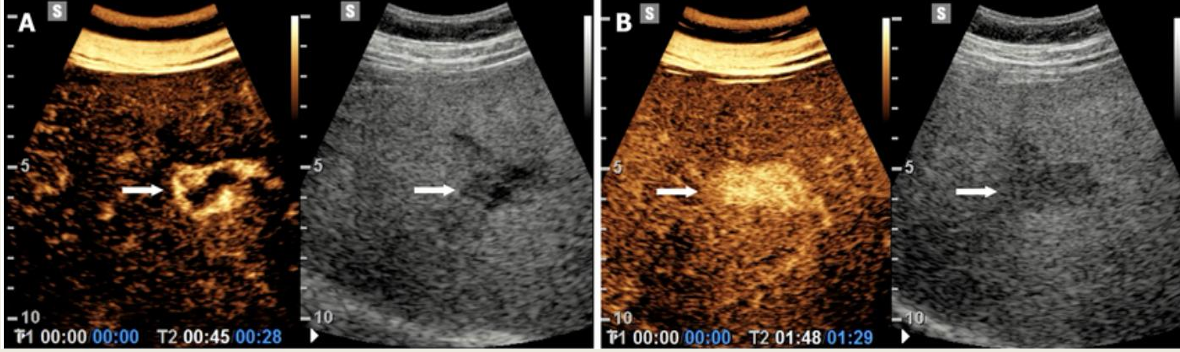

what lesion is seen on this CEU?

Hemangiomas